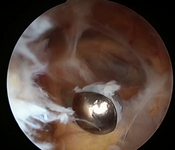

Arthroscopic resection of a popliteal cyst

From the collection of Dr John Kelly IV; used with permission